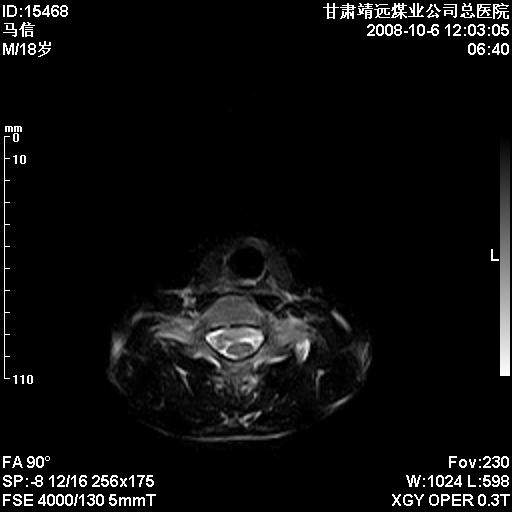

标题: MRI1827:颈椎内异常信号,是不是占位。

患者18岁,学生,在玩耍中受伤来检查,患者喜欢打篮球。颈椎内异常信号影,我们考虑占位,但是不像占位,又考虑硬膜囊的增厚,大家关建看颈椎椎管内的那个异常占位信号

腰椎的改变是不是正常发育的改变,还是打篮球的长期慢性损伤。

考虑 c3-4 c4-5 c5-6椎间盘突出,l3-4 l4-5 l5-s1椎间盘变性

后纵韧带增厚,颈2/3、3/4、4/5、5/6椎间盘变性、突出;椎体有旋转,提示椎小关节有问题;腰椎间盘变性,许莫氏结节。

椎体终板骨骺炎可能性大!支持!